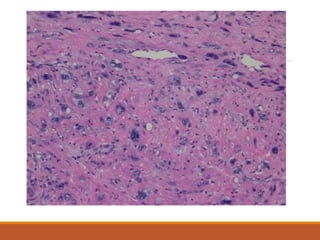

Squamous cell carcinoma

moderately differentiated non-

keratinising carcinoma.

Squamous cell carcinoma moderatelydifferentiated non- keratinising carcinoma.